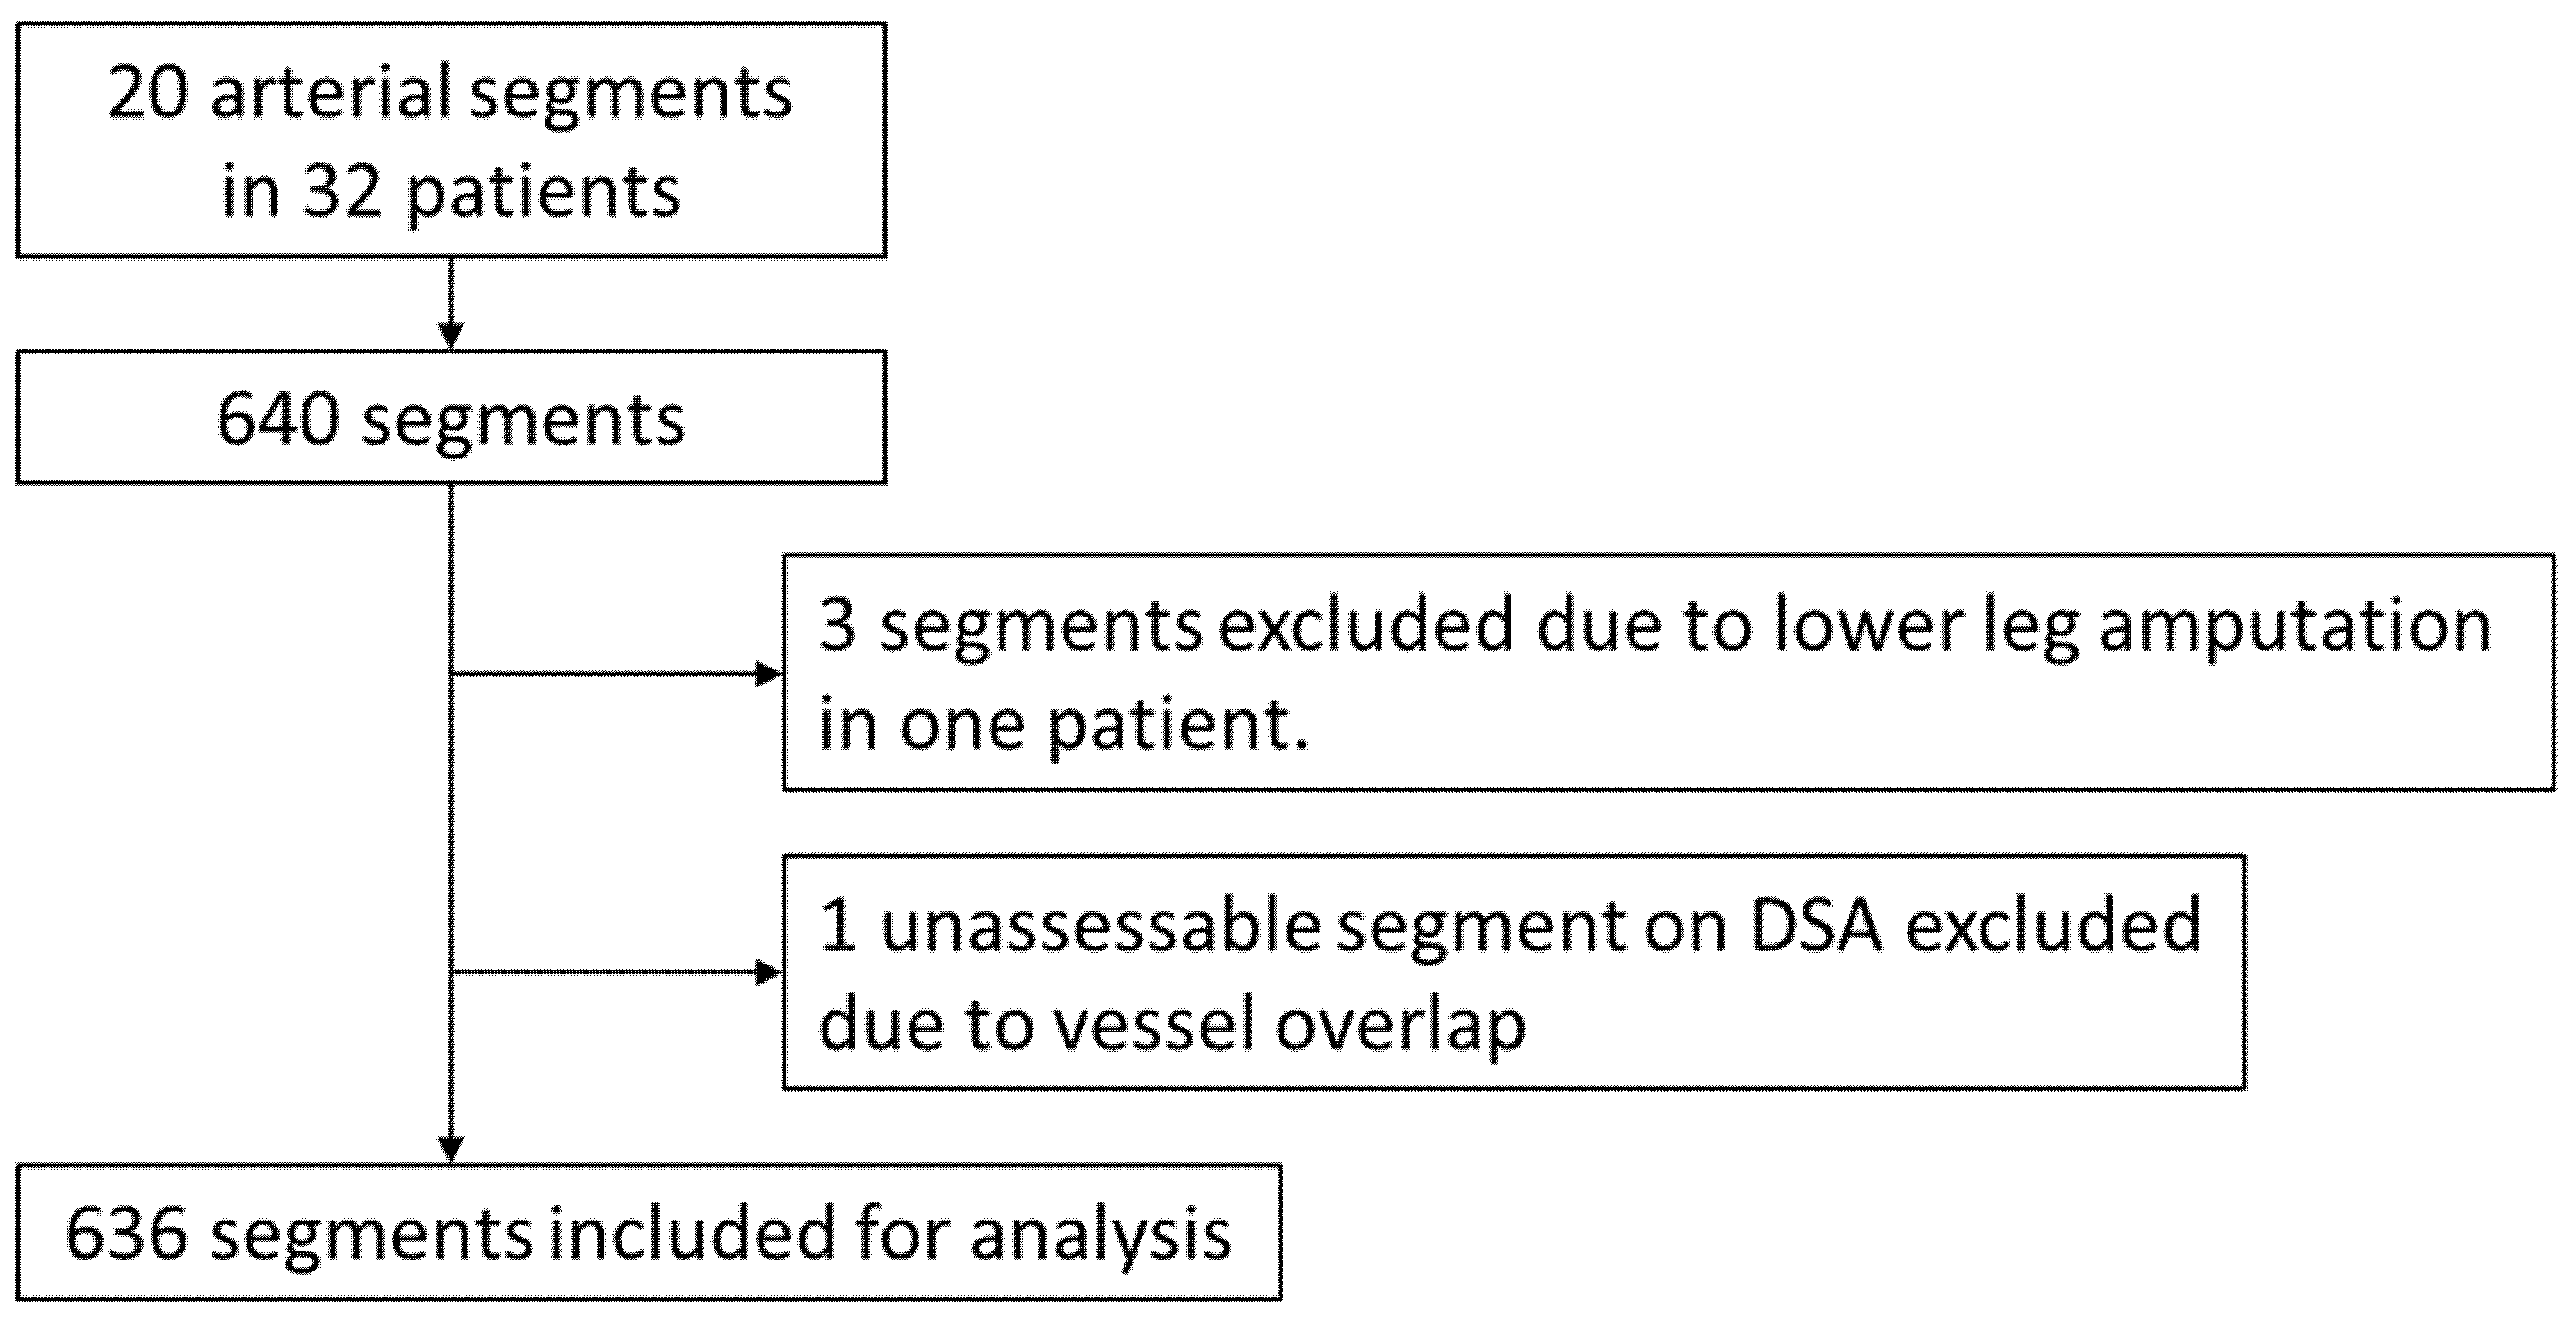

2.1. Study Design and Patient Population